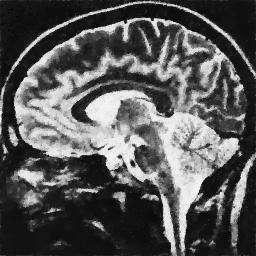

4.1. Uniform Gaussian noise

In this first experiment, we consider the denoising problem with brain scan images. The first set consists of images of pixels and Gaussian noise with zero mean and variance . The original and noisy images are shown in Figure 4.1. The domain decomposition-semismooth Newton algorithms run with the parameter values , , and . The results are shown in Figure 4.2. From the surface representation of , we can observe that is continuous and its shape is related to the one of the original image. In particular, the regularization is stronger in homogeneous regions in the image, and weaker where the image intensity undergoes variations on a smaller scale.